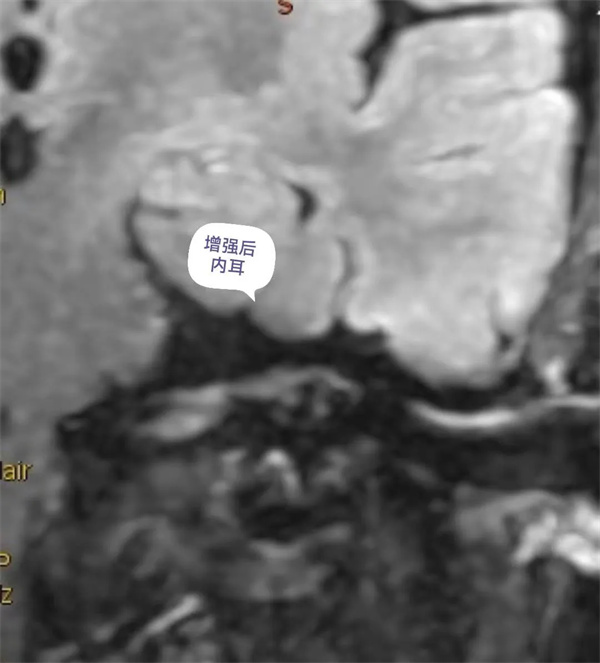

患者面肌痙攣,聽力減弱,行內(nèi)耳磁共振成像檢查。(如下圖所示)。

圖12:增強后內(nèi)耳外淋巴液磁共振顯示圖。